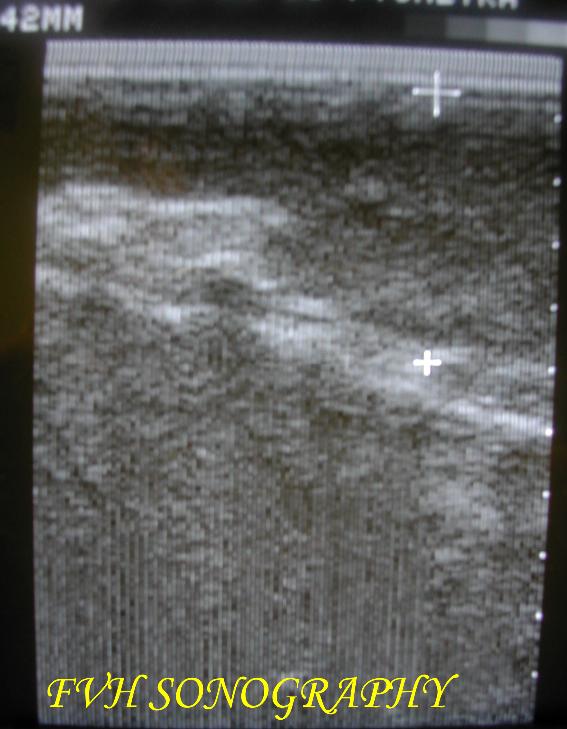

圖一 貓淋巴腫瘤的超音波影像腫瘤大小約為4.2cm